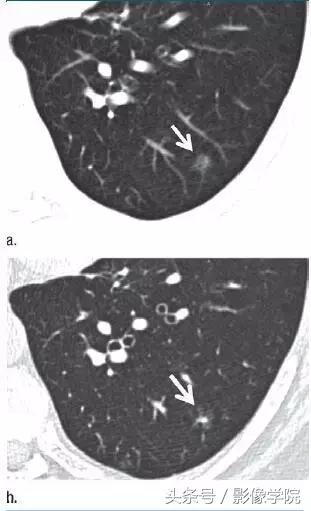

3、可疑部分实性结节

图 3(a)层厚 5 mm 的 CT 横断面图像,显示左肺下叶有明显的纯磨玻璃样结节(箭头)。(b)同一水平层厚 1 mm 的 CT 横断面图像,显示病变为一伴有囊性成分(箭头)的可疑部分实性结节。